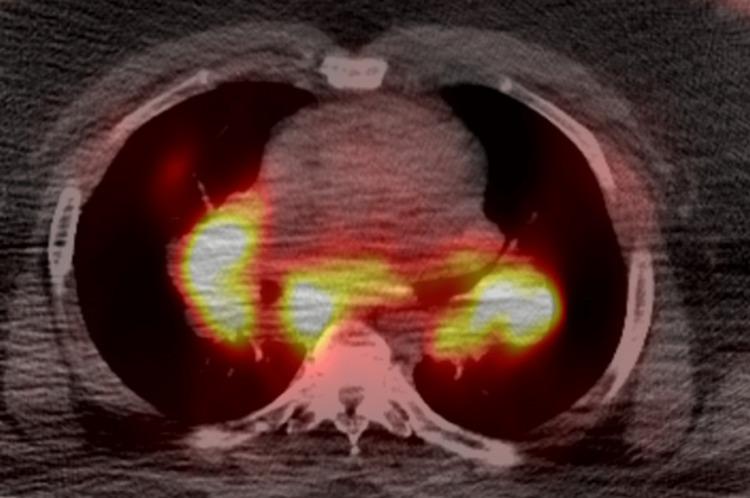

Sarcoidosis is a multisystem inflammatory disorder characterized by the formation of non-caseating granulomas. Hematological manifestations such as thrombocytopenia are unusual presentations of the disease. Various theories have been proposed for the development of thrombocytopenia in patients with sarcoidosis such as decreased production in bone marrow caused by granuloma formation, hypersplenism, and immune thrombocytopenia (ITP). We present a case of a 30-year-old African American male with ITP secondary to sarcoidosis who presented with a sudden onset of buccal mucosa and mucocutaneous bleeding and was found to have severe thrombocytopenia with values reaching as low as 1000/uL without prior history of easy bruising or bleeding. Overall, our patient had dyspnea, mucocutaneous bleeding, and was found to have mediastinal and hilar adenopathy, isolated thrombocytopenia, no splenomegaly, and non-necrotizing granulomas in the lymph nodes. The patient received platelet transfusions without initial response and received intravenous immunoglobulin (IVIG), romiplostim, and steroids with subsequent improvement in the platelet count after sufficient administration of a treatment regimen of approximately one week. Confounding factors that resulted in diagnostic uncertainty of our patient presentation included travel history with prophylactic antimalarial medications, doxycycline usage, only slightly elevated Angiotensin-Converting Enzyme (ACE) levels, and imaging features concerning metastatic disease vs. lymphoma. The clinical diversity of sarcoidosis often leads to diagnostic uncertainty and treatment delays due to its resemblance to other more common disorders. This is a novel case report of the earliest temporal presentation of severe thrombocytopenia and sarcoidosis in an African American male reported in the literature.

结节病是一种多系统炎症性疾病,其特征是形成非干酪样肉芽肿。血小板减少等血液学表现是该疾病不常见的表现形式。关于结节病患者血小板减少的发生提出了各种理论,例如肉芽肿形成导致骨髓生成减少、脾功能亢进和免疫性血小板减少症(ITP)。我们报告一例30岁非裔美国男性病例,该患者因结节病继发ITP,表现为颊黏膜和皮肤黏膜突然出血,发现有严重血小板减少,数值低至1000/μL,既往无易瘀伤或出血史。总体而言,我们的患者有呼吸困难、皮肤黏膜出血,发现有纵隔和肺门淋巴结肿大、孤立性血小板减少、无脾肿大以及淋巴结中有非坏死性肉芽肿。患者接受血小板输注后最初无反应,随后接受静脉注射免疫球蛋白(IVIG)、罗米司亭和类固醇治疗,在给予约一周的治疗方案后血小板计数随后有所改善。导致我们患者临床表现诊断不确定性的混杂因素包括有预防性抗疟药物的旅行史、使用强力霉素、血管紧张素转换酶(ACE)水平仅略有升高以及关于转移性疾病与淋巴瘤的影像学特征。结节病的临床多样性常常因其与其他更常见疾病相似而导致诊断不确定性和治疗延迟。这是文献中报道的首例非裔美国男性最早出现严重血小板减少和结节病的病例报告。